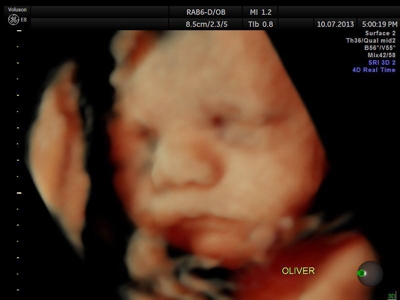

La ecografía 4D HD/5D consiste en la adquisición y presentación continúa de volúmenes. La denominación de la técnica obedece a que hay cuatro dimensiones involucradas: ancho, largo, profundidad y tiempo.

Si bien la Ecografía 4D HD/5D puede realizarse en cualquier etapa del embarazo, recomendamos realizarla entre las semanas 24 a 32 de gestación ya que se pueden observar rasgos bien definidos en el bebe.

Fotografías de ecografías 4D HD/5D

Haga click sobre las imágenes para ampliar